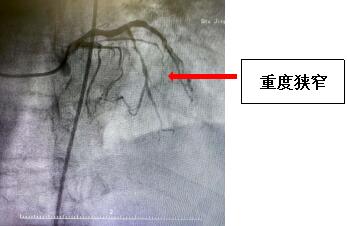

2024年3月24日,患者田某某,在家中突然感觉心前疼痛、气短,上腹部、剑突下疼痛,伴呕吐,当时来我院急救中心就诊,值班医师对其进行心电图检查,结果显示ST段抬高,立即请心血管内科医生进行会诊,考虑急性心肌梗死!建议住院进一步检查。办理住院后,对患者进行了进一步检查,经综合评估需对患者立即进行手术。但考虑患者年龄较大,随时有消化道、颅内出血风险。高龄患者血管脆性增加、动脉硬化严重,又突发急性心梗,手术风险极大,极有可能在手术过程中心脏破裂死亡。但不进行手术,进行保守治疗,随时可能出现心梗面积增大、严重心衰、恶性心律失常,也面临死亡风险。该如何抉择,患者病情极其危重,随时有生命危险。高四红主任医师带领心血管内科介入团队立即组织讨论,并向家属详细告知病情及手术风险,制定可行性治疗方案,经家属同意后,在导管室的全力配合下对患者进行冠脉造影术及支架植入术。手术过程中患者右侧锁骨下动脉严重迂曲,造影导管无法到达冠脉口,介入团队当机立断,改变导管路径,穿刺股动脉进行冠脉造影,造影结果发现患者前降支近中段重度狭窄,右冠远端弥漫性狭窄,最严重处99%狭窄,评估血管情况明确患者系多支病变,心血管内科介入团队顶住压力,尽最大努力缩短手术时间,经过1小时努力,患者右冠血流恢复,治疗效果显著,胸痛、气短缓解。术后通过心内科医护人员的精心治疗,患者康复出院。